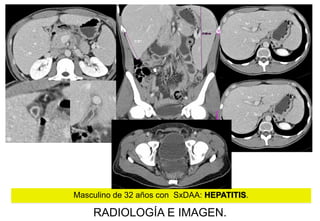

Masculino de 32 años con SxDAA: HEPATITIS.

RADIOLOGÍA E IMAGEN.